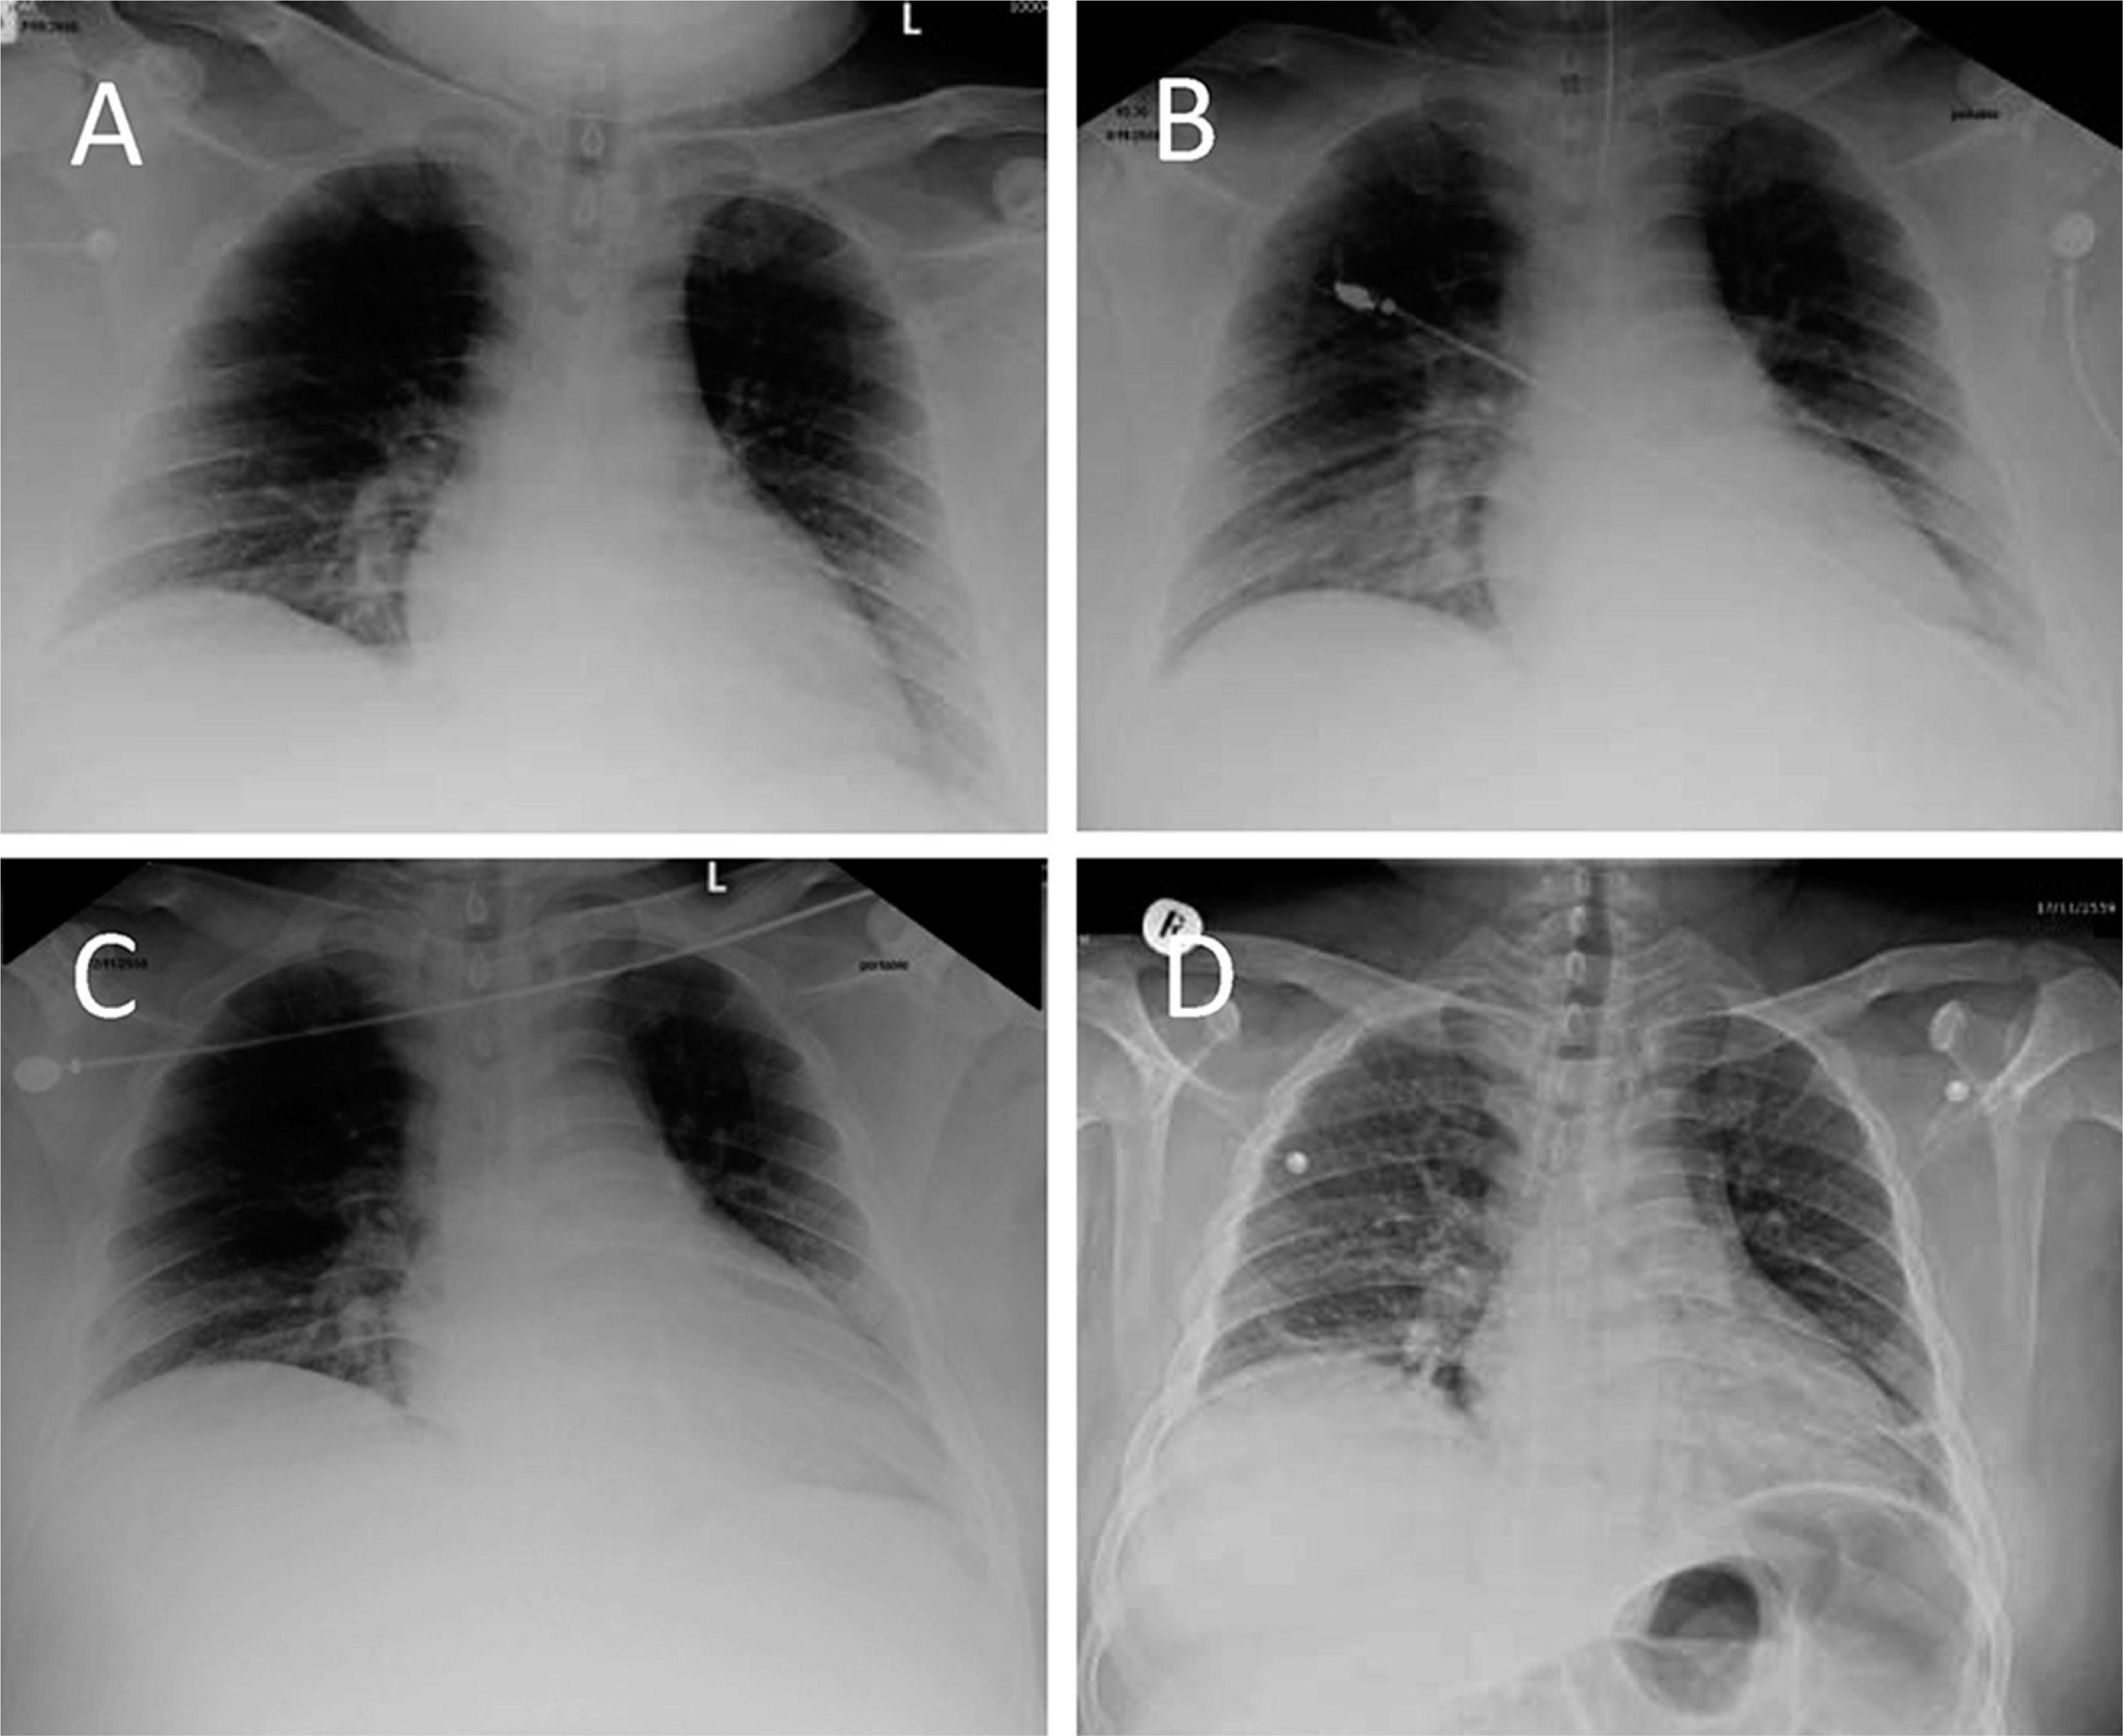

Progression of an autoimmune hemolytic anemia that developed during severe dengue infection